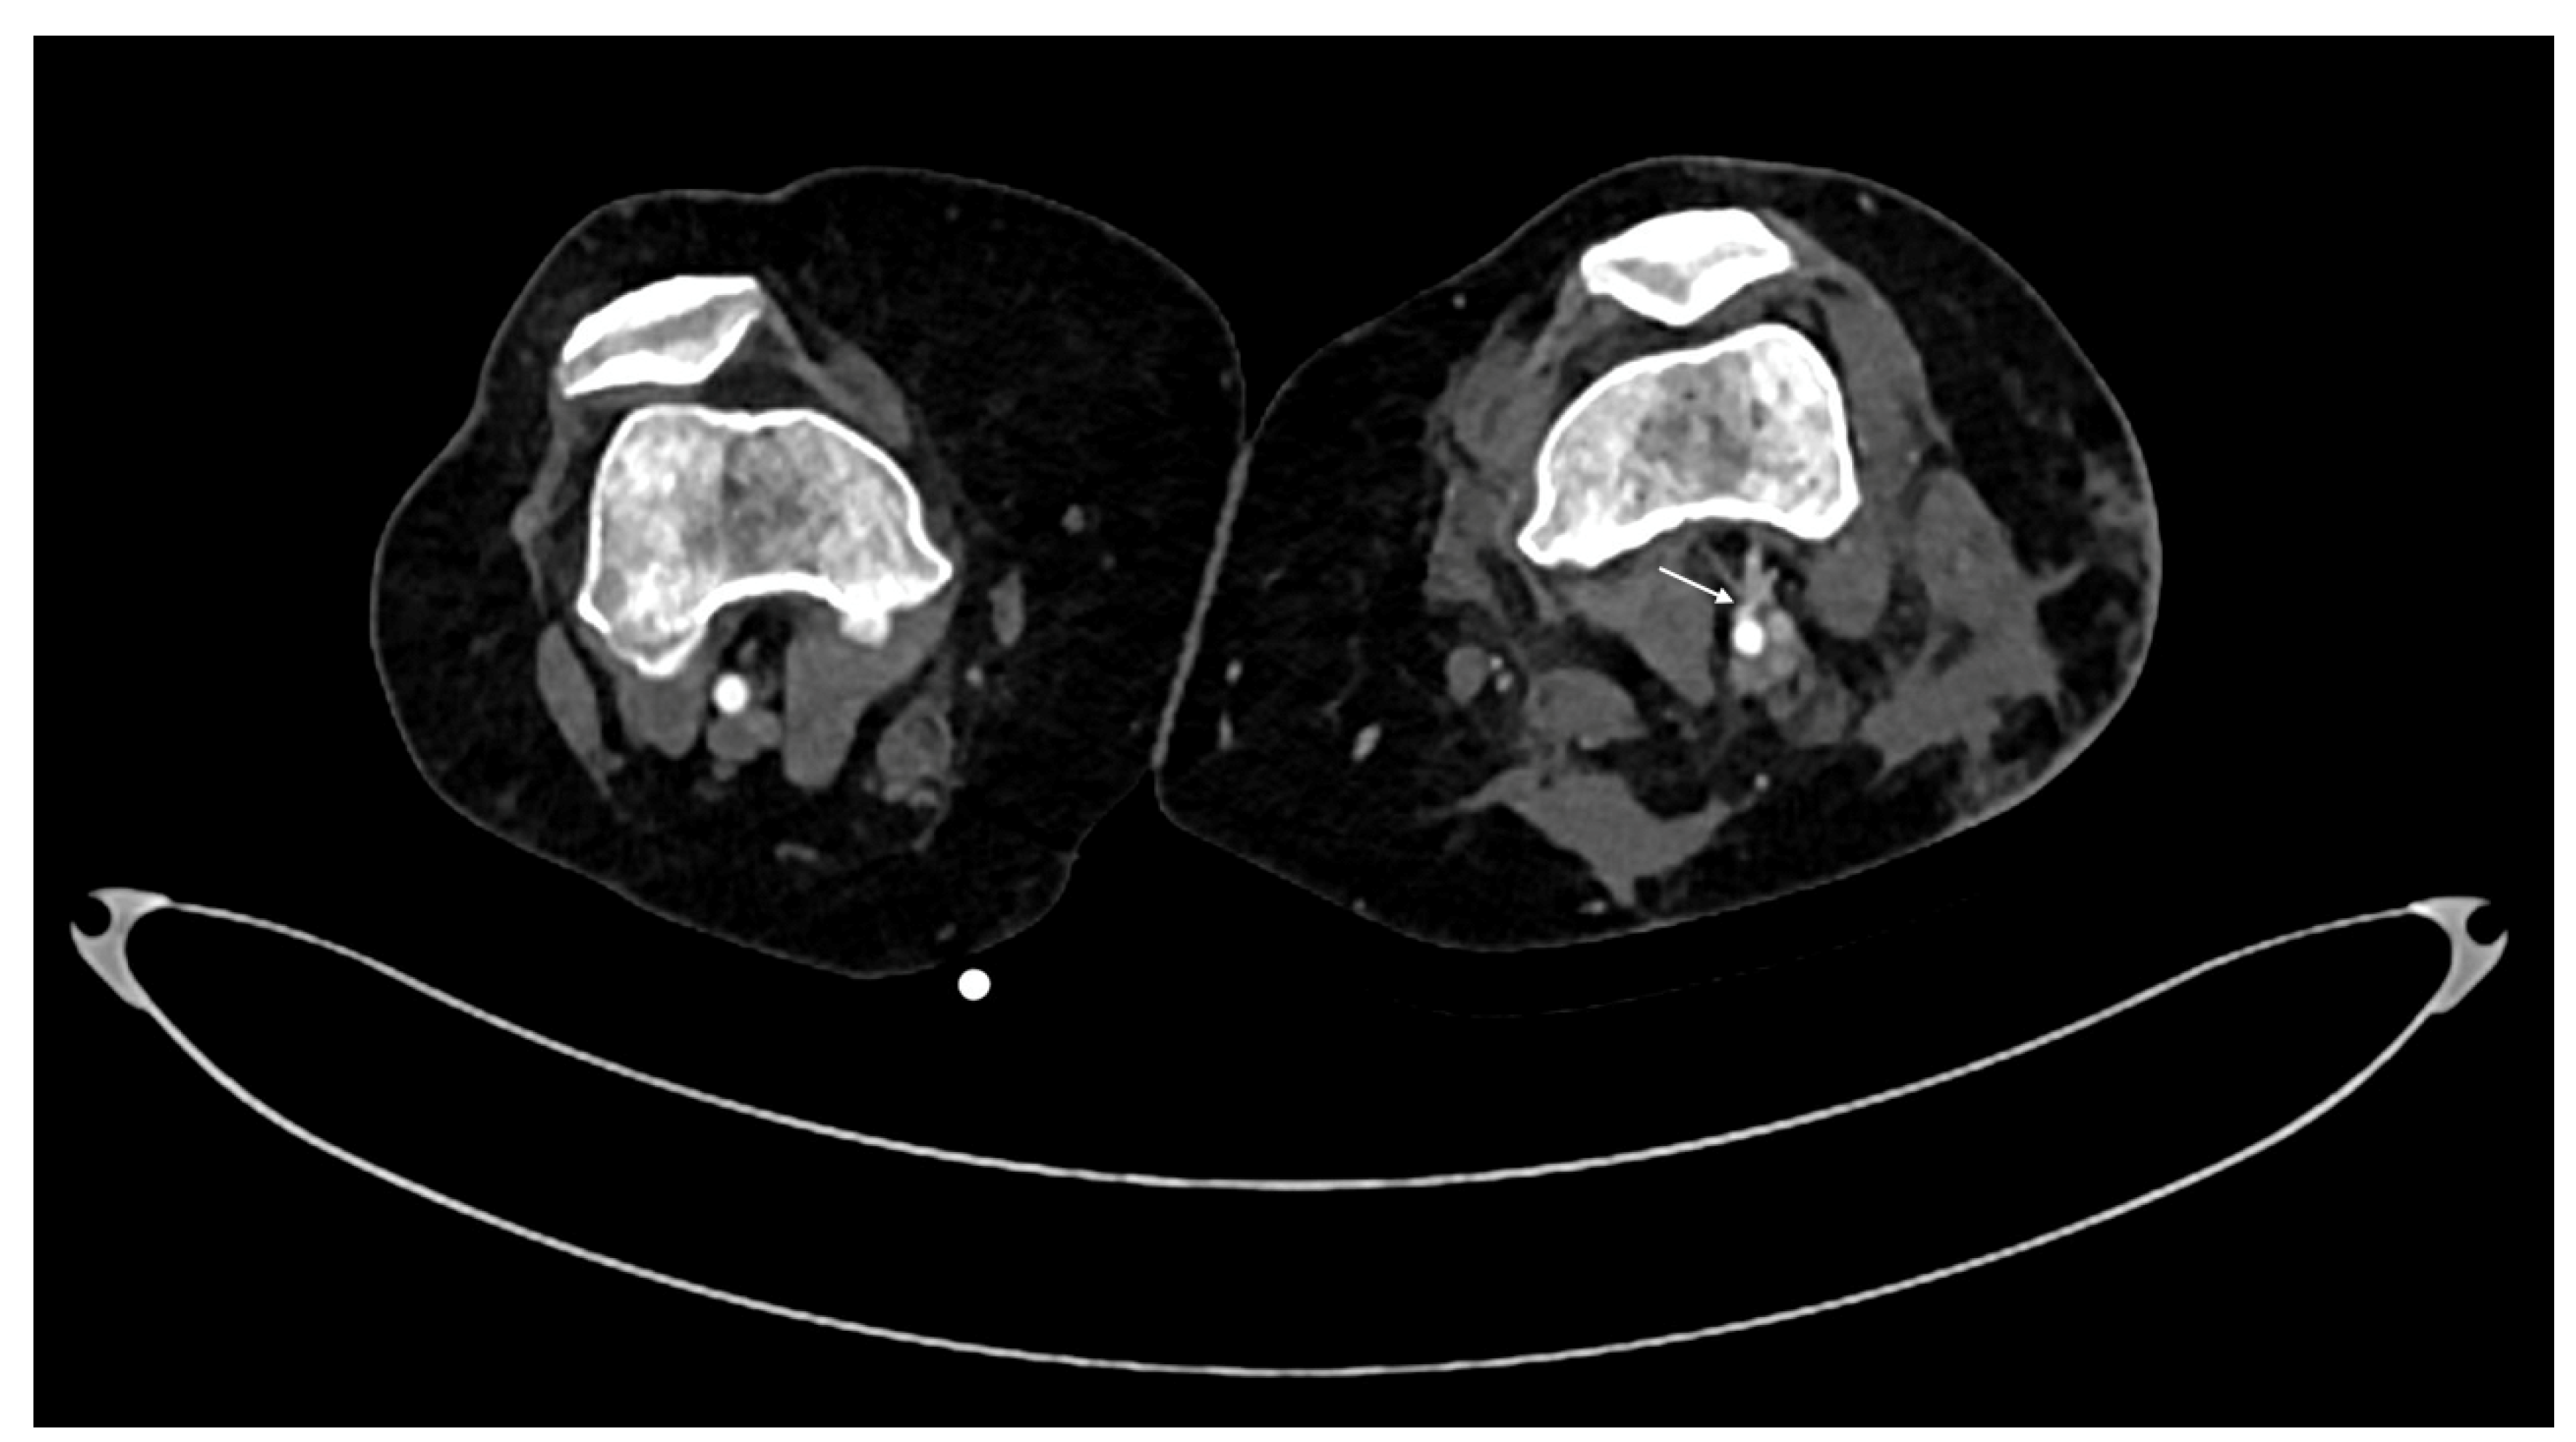

- Pseudoaneurysm is caused by focal arterial wall tear involving intimal and medial layers, and represents a collection of blood contained only by the adventitia layer or surrounding tissue [5,56,59]. It appears as an outpouching sac with a round and smooth margin in continuity with the arterial adjacent lumen (Figure 4). Pseudoaneurysm bleeding appears as irregular, lobulated perilesional contrast blush [65,68]. Pre-exiting calcification or pseudoaneurysm should be differentiate form active bleeding; delayed phase acquisition can be useful because in active bleeding the contrast extravasation dissipates along tissue planes instead pseudoaneurysm and calcification remain stable [60,67].